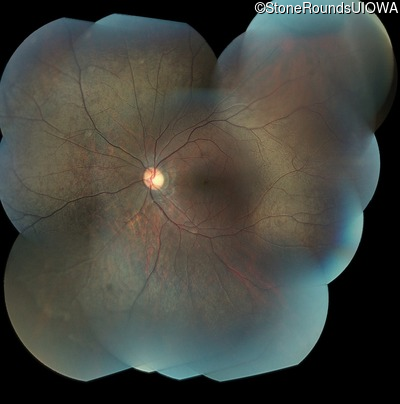

Fundus Montage - Right - 20/25 -3

Exemplar

Fundus Montage - Left - 20/30 +2